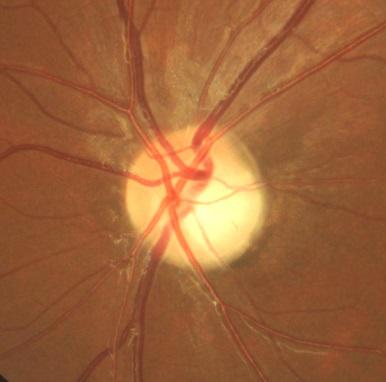

视神经病变